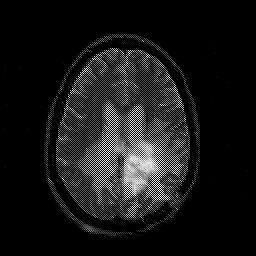

Glioblastoma multiforme overlay -- Slice #34

[Home][Help][Clinical][Tour 1][Tour 2][Tour 3] Slice 34